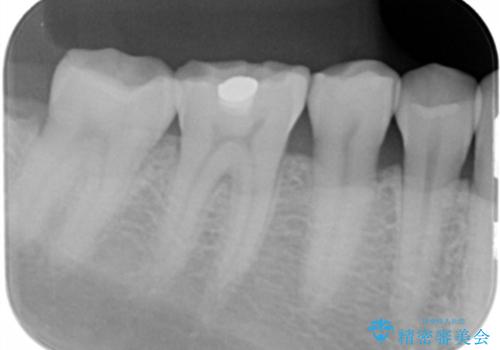

- 奥歯がしみるとのことで来院。レントゲンを確認したところ虫歯はなかったが、歯の咬む面がすり減っていました。

歯ぎしりがとても強い方で、セラミックの詰め物だと割れてしまう可能性があることを伝えたところ、なるべく割れにくいものが良いとのことでしたので、ゴールドインレーによる治療を行いました。